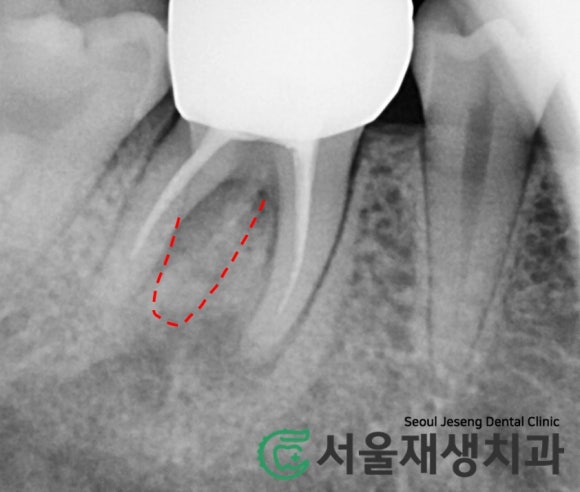

CT 촬영

염증이 몹시 커서

인접 해부학적 구조물과의

연관성을 평가해야 하거나,

위 사례처럼 접근이 어려운 신경의

위치를 파악하기 위해 CT를 촬영합니다.

신경치료 중의 CT 촬영은 대개

건강보험이 적용되어 본인 부담금은 2만원 전후에 불과합니다.

CT를 확인해보니,

치근단염증이 점점 퍼져서

잇몸뼈를 뚫고 나간 것이 보입니다.

그것이 마치 여드름처럼

잇몸으로 불거져 나오는 것이지요.

찾았습니다!

평면 엑스레이에서 의심되었던

'미치료 신경'의 위치를

CT를 통해 정확하게 파악합니다.

이제 남은 것은 미세현미경을 통한

꼼꼼한 재신경치료!